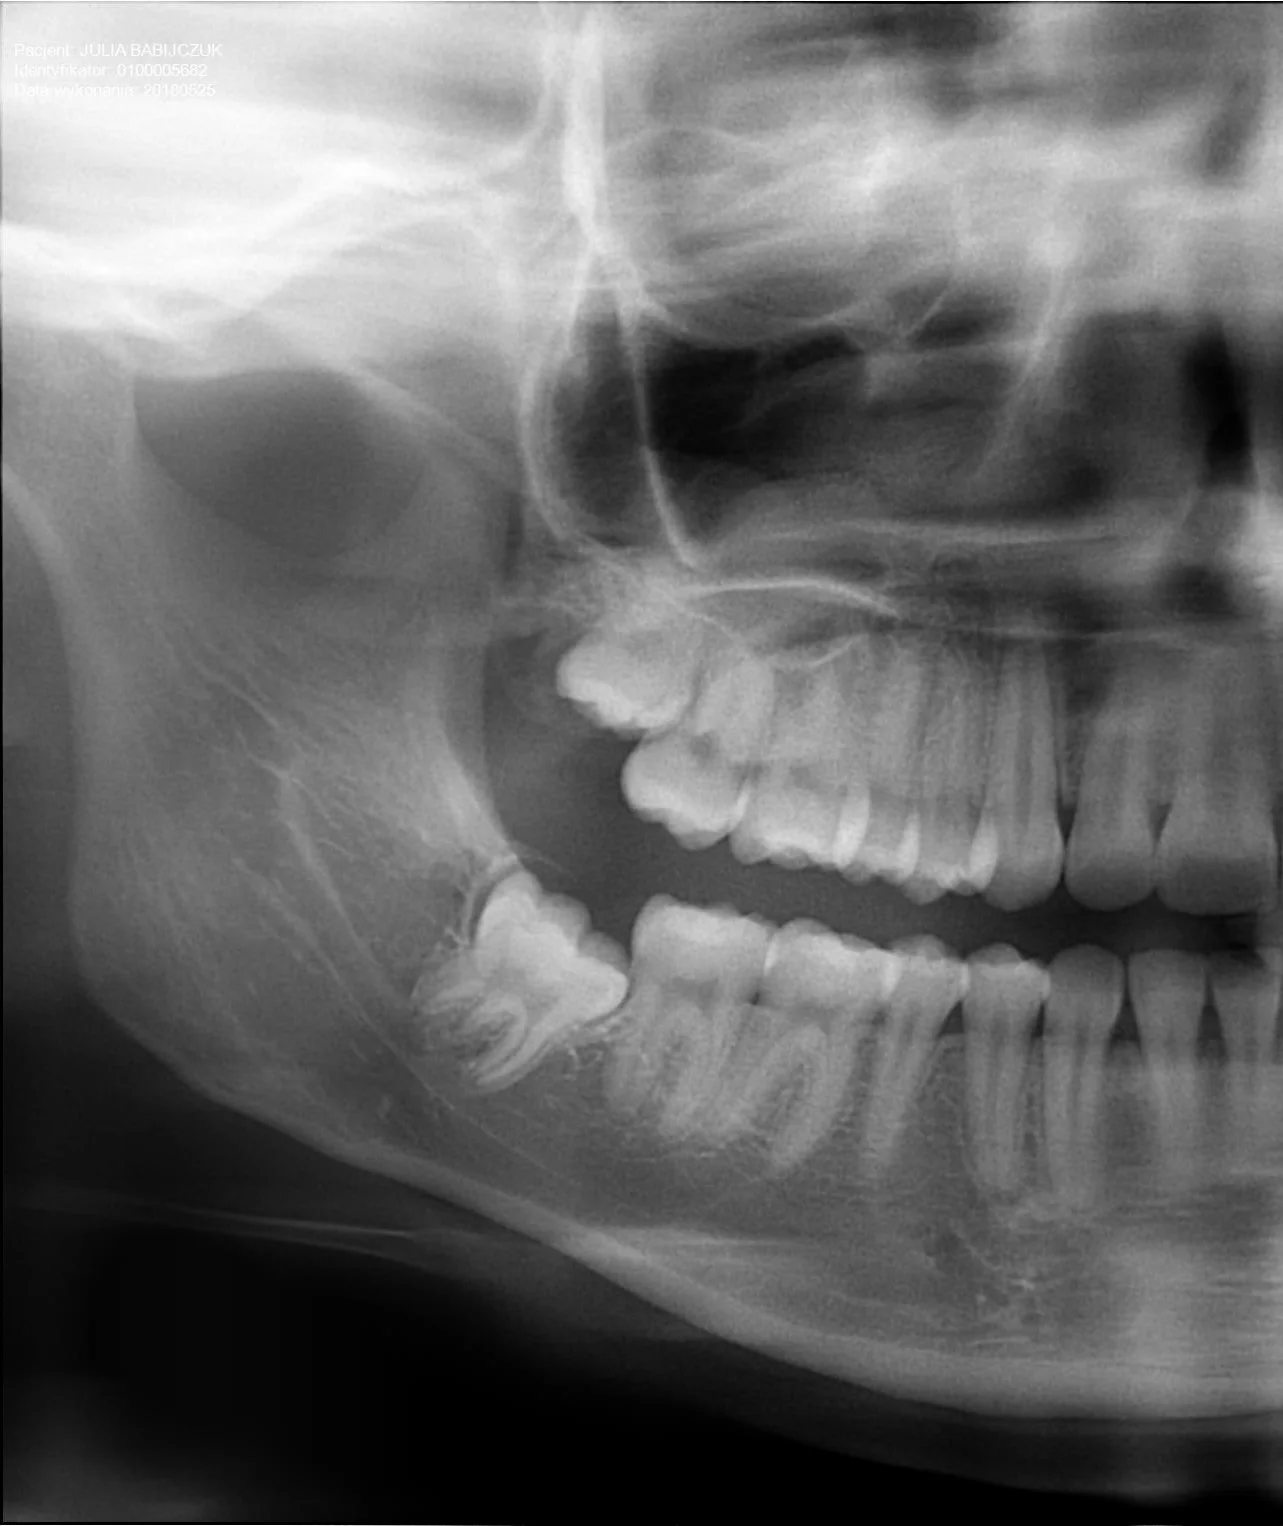

Po

Profesjonalna chirurgia stomatologiczna z widocznym efektem leczenia

Każdy zabieg poprzedzony jest dokładną diagnostyką, najczęściej w oparciu o zdjęcie RTG pantomograficzne lub CBCT 3D. Dbamy o bezbolesny przebieg, komfort pacjenta oraz szybkie gojenie poprzez stosowanie nowoczesnych technik chirurgicznych.